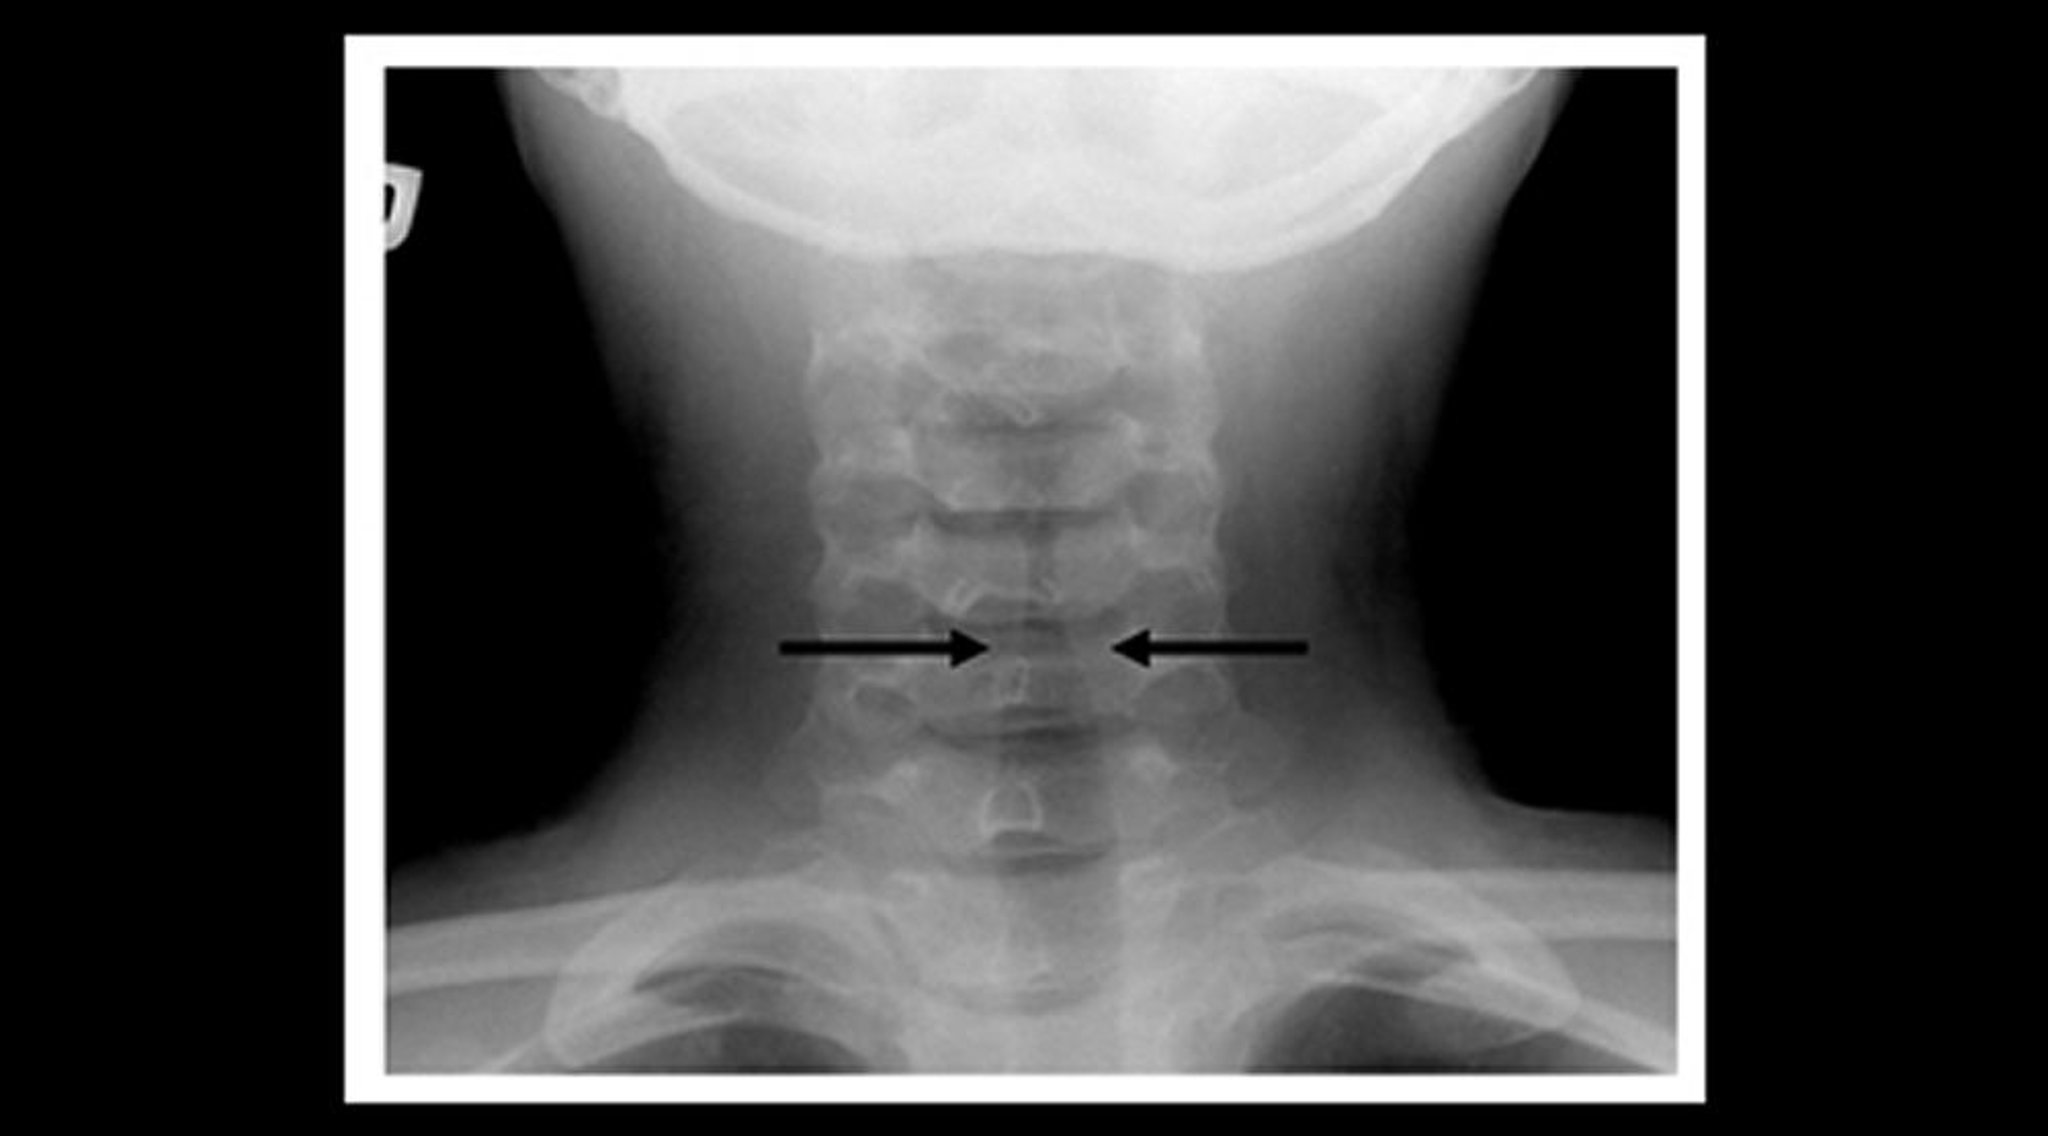

Radiograph of a Child With Croup (Coronal View)

Soft-tissue neck radiograph of a child with croup shows gradual narrowing of the subglottic tracheal air shadow (steeple sign—arrows) and dilation of the pharyngeal air spaces.

Image courtesy of John McBride, MD.